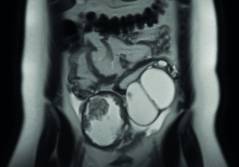

Sonoquiz 03/23

Was fällt kaudal des Nabels auf? PDF Dokument

Auflösung Sonoquiz 03+04/2023

Auflösung Sonoquiz aus diesem Heft PDF Dokument